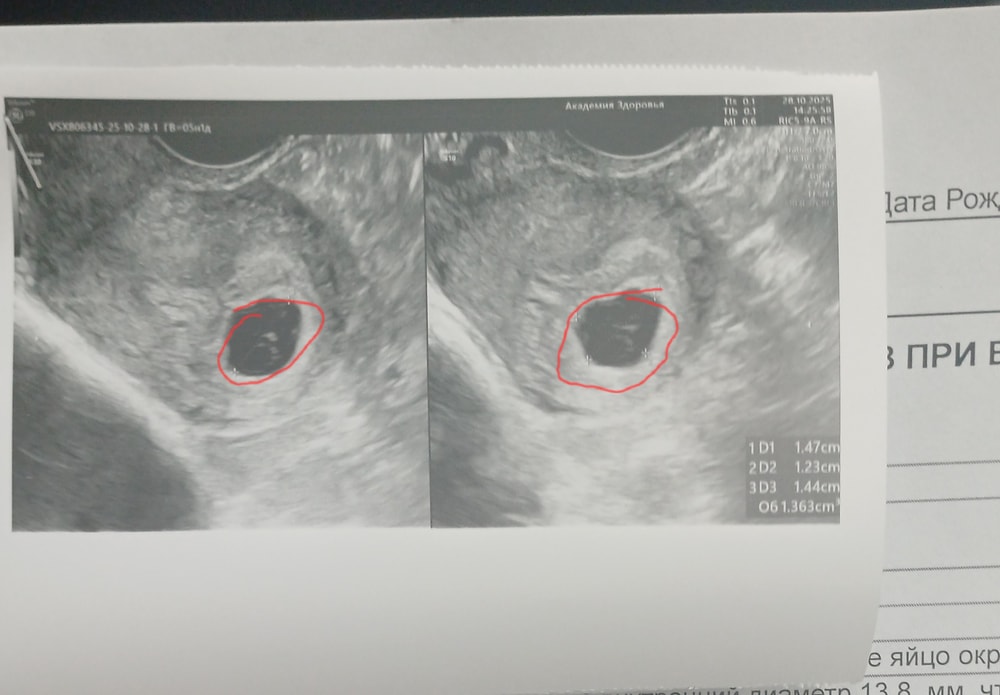

Наталья , у меня так,пока внутри пусто Изображение

Незабудка , у вас плодное яйцо то маленько ещё чтобы что-то увидеть, как раз оно и на 5 недель и есть, в 4 недели вообще точкой на узи выглядит.

Наталья, врач 9.4мм намерила 🙈